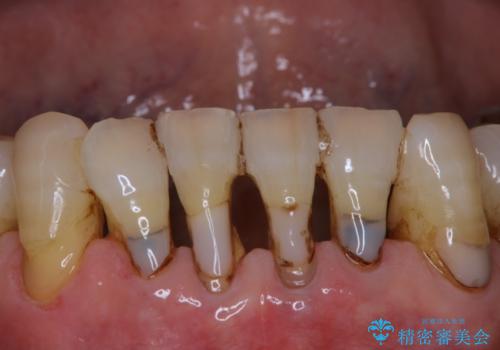

セラミックインレー・セラミッククラウンによる虫歯治療

- 右上5番目の歯が欠けたので治療してもらいたいといらっしゃった方の症例です。

右上5番目の歯は樹脂による土台を築造後、セラミッククラウン(エコノミー)で補綴を行いました。

右上6番目の歯は虫歯があったため、セラミックインレーによる修復を行いました。

- セラミックインレー…¥70,000、オールセラミッククラウン(エコノミー)…¥70,000費用は治療当時の料金となります